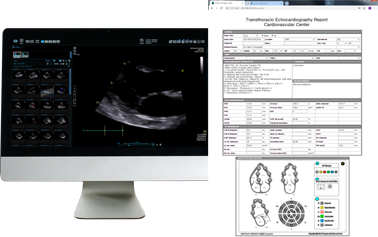

– Web 시스템과의 연동 : Web 수행 작업 공유 및 리포트 시스템 연동이 가능합니다.

– 맞춤형 리포트 시스템을 지원합니다.

– 사용자와 미팅을 통한 맞춤형 서비스 지원 및 지속적인 데이터 관리가 가능합니다.

– 맞춤 항목 설정을 통한 검색과 xlsx를 지원하는 추출 시스템을 통한 데이터 관리가 가능합니다.